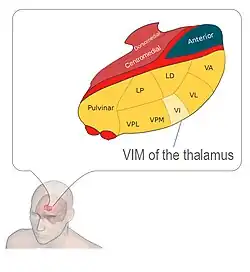

DBS is used to manage Parkinson's disease symptoms that are resistant to medication.[20][30] The ideal candidate for DBS is one that does not have dementia, is not severely depressed, and who does not have falls while being in their best on-drug state, but who do have disabling motor fluctuations or dyskinesias that necessitate bilateral surgery.[1] It is treated by applying high-frequency (> 100 Hz) stimulation to target structures in the deep subcortical white matter of the basal ganglia. Frequently used targets include the subthalamic nucleus (STN), globus pallidus internus (GPi) and ventrointermediate nucleus of the thalamus (VIM). Neurostimulation can be considered for people who have Parkinson's with motor fluctuations and tremors inadequately controlled by medication, or to those who are intolerant to medication as long as they do not have severe neuropsychiatric problems.[31] A >30% degree of symptom responsiveness to dopamine is a strong predictor of a good response to DBS surgery, though it is not mandatory. This has led most centers to require evaluation both on and off dopamine prior to the procedure to increase the likelihood of success.[32] DBS is not currently considered to be a disease-modifying treatment.[33] Shorter disease duration pre-operatively tends to lead to better results after surgery. The response from DBS is only as good as the patient's best "on" time, with the exception of tremor, which may show greater improvement than that seen with medication.[34]

Parkinsonian Tremor

Frequencies above 100 Hz are most effective for cessation of tremor, while lower frequencies have less effect.[107] In clinical practice, frequencies between 80 and 180 Hz are typically applied. DBS electrodes commonly target the ventrointermediate nucleus of the thalamus (VIM) or ventrally adjacent areas in the zona incerta or posterior thalamus. Multiple targets along the circuitry of the cerebellothalamic pathway (also referred to as the dentatorubrothalamic or dentatothalamic tract) have been shown to have similar therapeutic effect.[108][109][110]

| Essential Tremor (or Parkinsonian Tremor) | July 31, 1997 | Approved for essential tremor. | Ventral intermediate nucleus of the thalamus (VIM) | Significant tremor reduction with thalamic DBS in patients with essential tremor, long-term efficacy and safety.[195] | FDA |